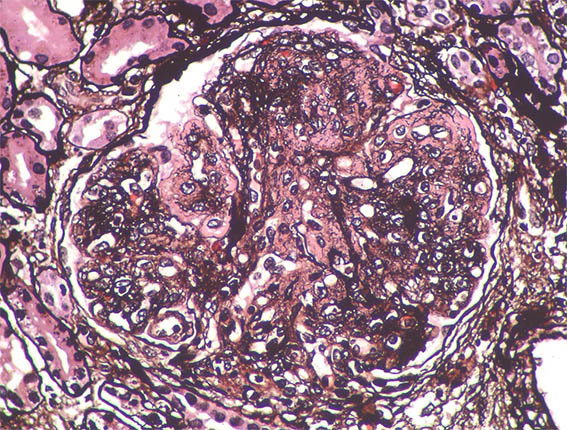

A 33-year-old man presented with pedal edema, persistent proteinuria and hypertension. Her past and family histories were unremarkable. Her blood pressure was 160/100 mm Hg. Physical examination revealed pedal and facial edema, without other alterations. Laboratory tests showed proteinuria of 4.7g/24 h, serum creatinine 1,0 mg/dL, microhematuria, normal serum complement levels, ANA negative; HIV, hepatitis B and C viral infections were negative. Ultrasound of the abdomen showed normal sized kidneys.

Kidney biopsy was performed. Look at the images.

Figure 5. Methenamine-silver stain, X400.